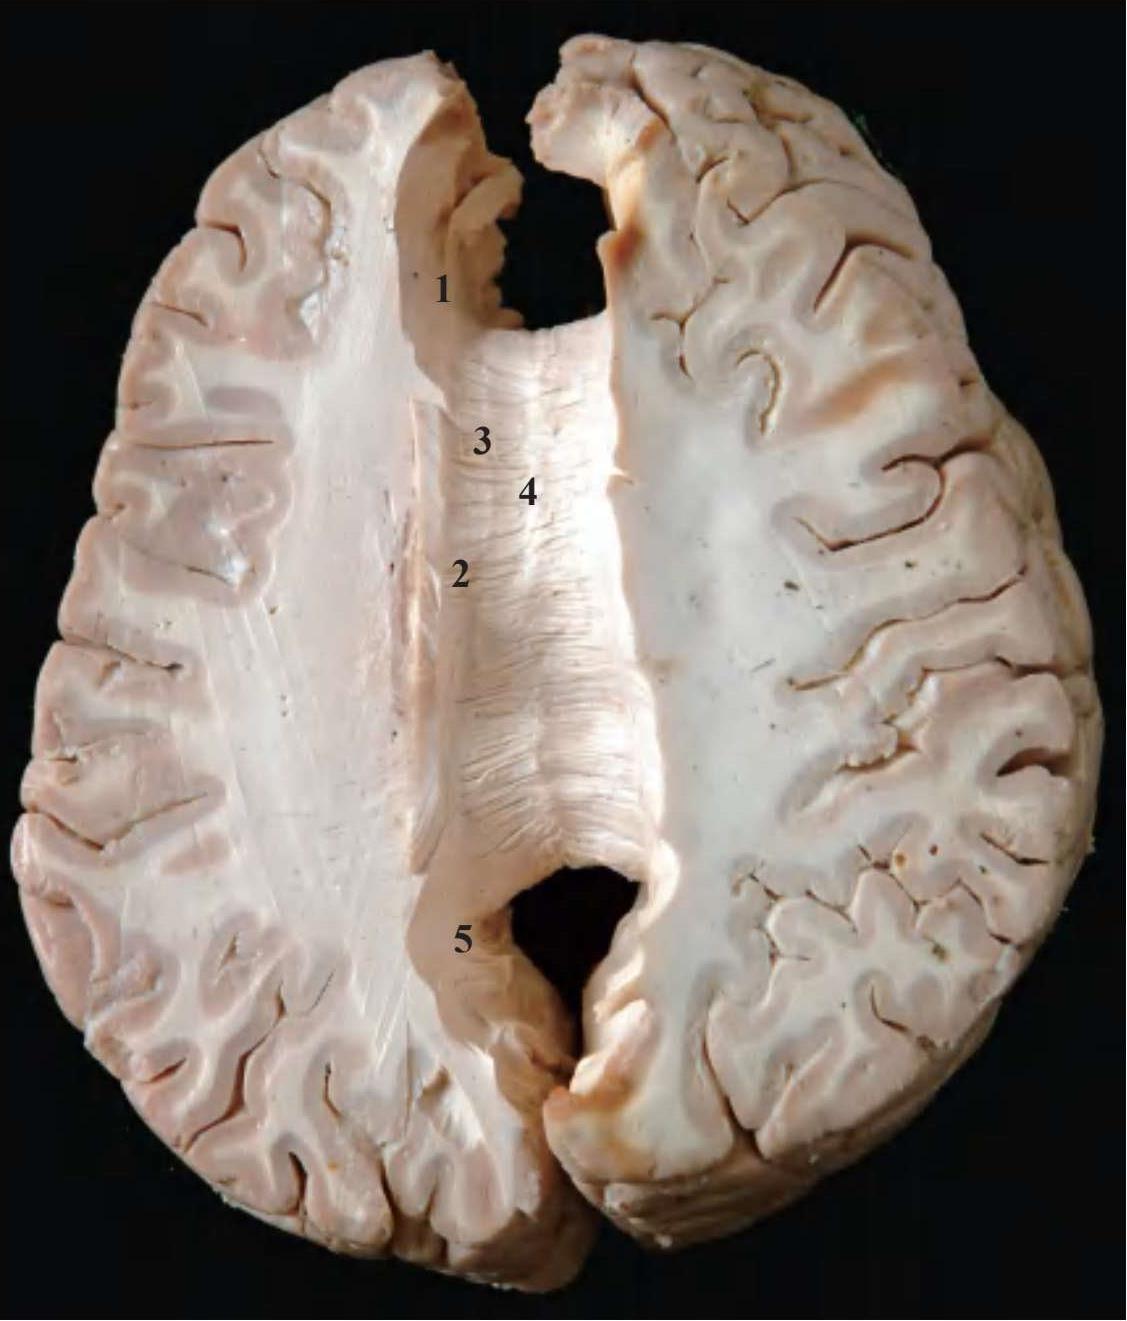

1.额钳 frontal forceps;2.胼胝体辐射 radiatio corporis callosita;3.内侧纵纹 medial longitudinal stria;4.外侧纵纹 lateral longitudinal stria;5.枕钳 occipital forceps

图2-10 连合纤维示胼胝体